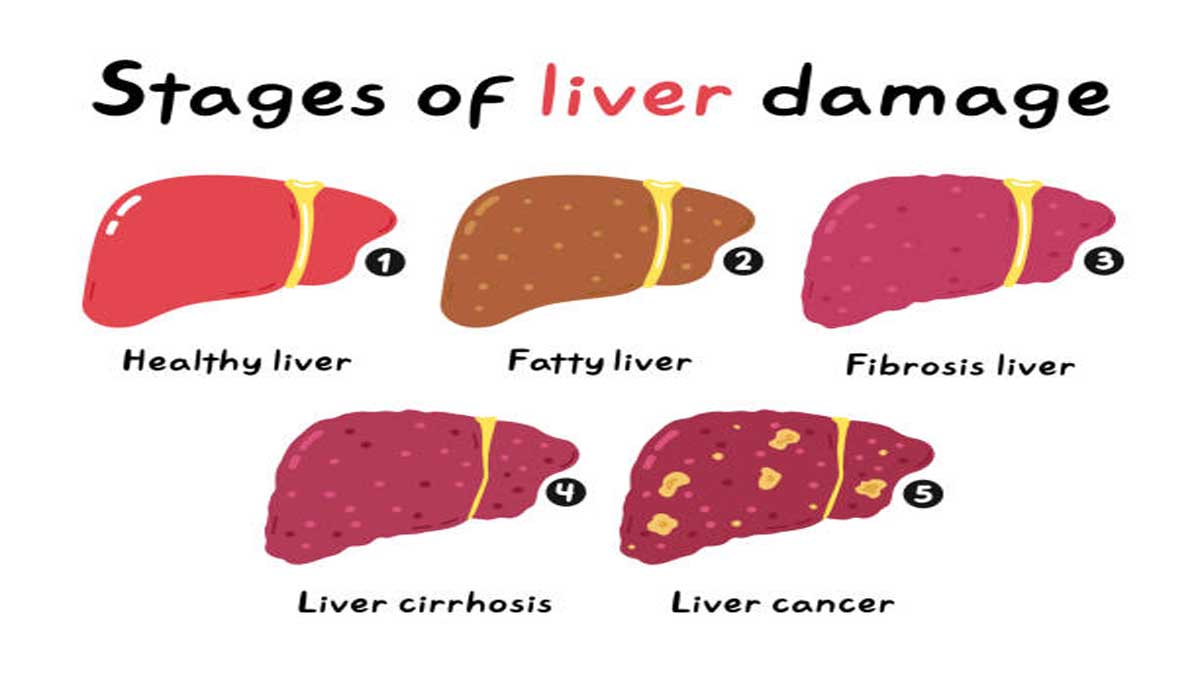

लिवर रोग के प्रकार

लिवर में सूजन आना। वायरस के संक्रमण के कारण। - फैटी लिवर डिजीज (Fatty Liver Disease)

लिवर में अत्यधिक वसा जमा होना। - सिरोसिस (Cirrhosis)

लिवर के ऊतकों में स्थायी क्षति और जख्म होना। - लिवर कैंसर (Liver Cancer)

लिवर में कैंसर कोशिकाओं का विकास। - ऑटोइम्यून लिवर डिजीज

प्रश्न 3: क्या फैटी Liver Disease खतरनाक है?

उत्तर: अगर समय पर इलाज न किया जाए तो फैटी लिवर गंभीर सिरोसिस या लिवर कैंसर में बदल सकता है।